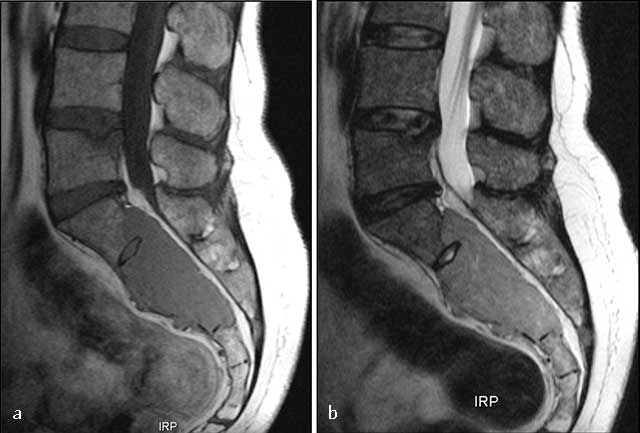

Figure 9

Sacral plasmocytoma. MR: (a) Sagittal T1-WI shows homogenous mass involving S1, S2 and S3 with intermediate signal intensity. (b) Sagittal T2-WI show a high signal intensity of the mass extending into the pelvis, epidural space, and posterior elements.